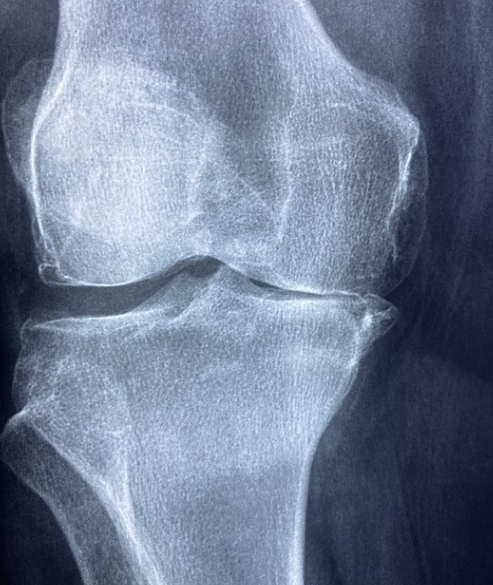

무릎 연골 관절에는 허벅지뼈와 정강이뼈가 맞닿아있다고 한다. 이들의 뼈 끝에 있는 골연골은 뼈가 서로 부딪히면서 손상이 되지 않도록 하는 역할을 하게 되는데, 우리가 무릎에 무리를 줄 수 있는 행동이나 운동을 반복하게되면 뼈를 감싸고 있는 연골이 손상되기 때문에 평소에 무릎이 자주 아프다면 아래에서 언급하는 무릎 연골 손상 대표적 증상 TOP 6에 대해서 알아보고 자신이 해당하는지 파악해보기 바란다.

무릎 연골 손상 대표적 증상들

여기에 언급된 증상들이 100% 정담은 아니지만, 대표적 증상들이며, 이 증상 이외에도 개인적인 증상은 다를 수 있으므로 병원에 방문해서 정확하게 진단을 받는 것이 가장 올바른 진단 방법이라는 것을 항상 인지하자.